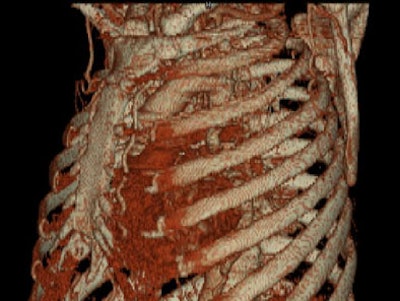

- Zoomed oblique volume-rendered images displayed the coarctation of the aorta, distal to the left subclavian artery. [Figure 6] [Movie 2] [Movie 3]

| Figure 6. |